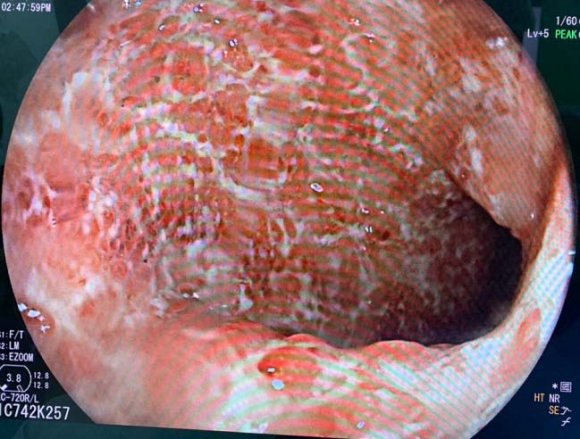

The patient was admitted again 6 months later, she developed bloody diarrhea with abdominal pain, and tenesumus, colonoscopy revealed inflamed hyperemic colonic mucosa with multiple active ulcers, Hemoglobin (Hb) was 9.1 g/dl (normocytic), white blood cell count was 12.44 × 103/ml (neutrophilic leukocytes: 90.8%, lymphocytes: 7.4%), and platelets were 3 × 105 /?l, C-reactive protein(CRP) and erythrocyte sedimentation rate were 78 mg/dl and 35 mm/h respectively. The patient was therefore treated with intravenous corticosteroids (1mg/kg/day) for 7 days then with PSL 50 mg/day, and azathioprine was switched to 6 mercaptopurine (6MP) 75mg/day, this was followed by clinical and biological improvement.

A year and two months later, the patient was admitted for an UC attack, she was having Bloody diarrhea as well as severe tenesmus and rectal bleeding, colonoscopy revealed inflamedfriable mucosa severely hemorrhagic. Bblood test reveled anemia with Hb: 8.4 g/dl (normocytic), white blood cell count was 15.333 x 10 3 /ml, CRP was 120 mg/dl, stool studies were negative for infection. Intravenous corticosteroids as well as corticosteroid and 5-ASA enemas were begun and the patient showed clinical and biological improvement (number of bloody diarrhea diminished as well as CRP (40 vs 120). The colitis was then considered an immunomodulator refractory colitis, and we had to consider another treatment to maintain remission.